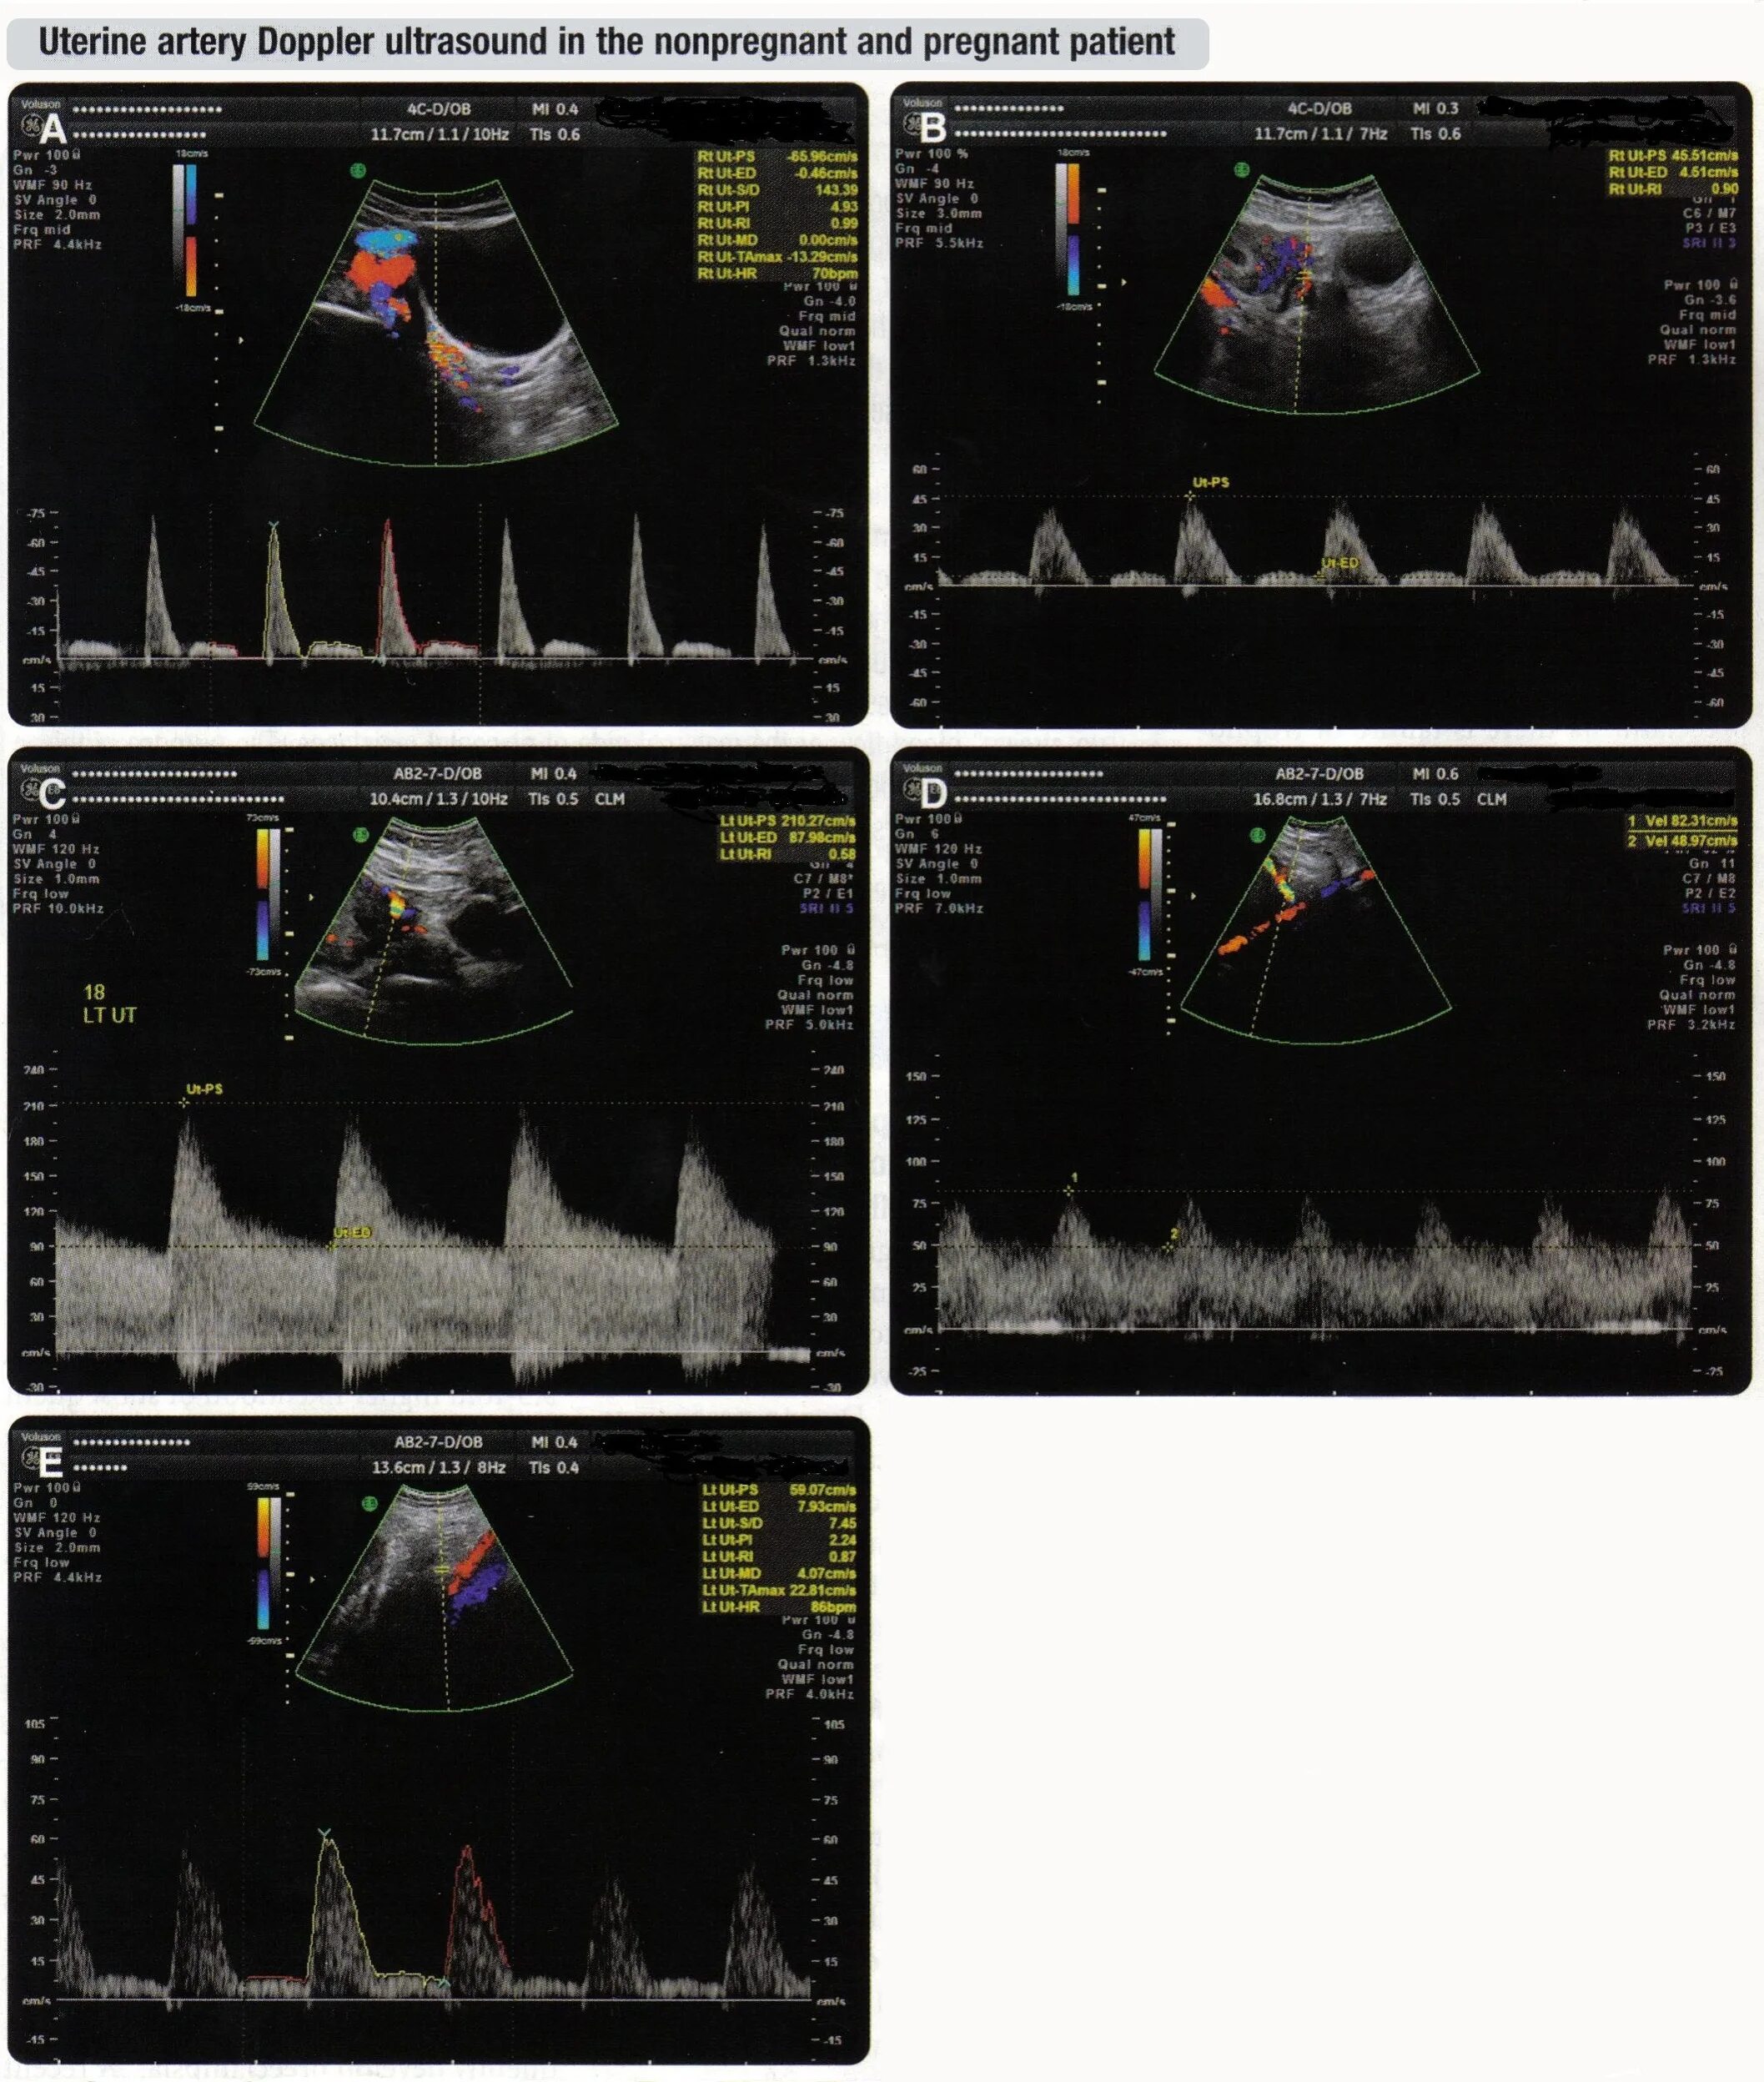

Допплерометрия маточных